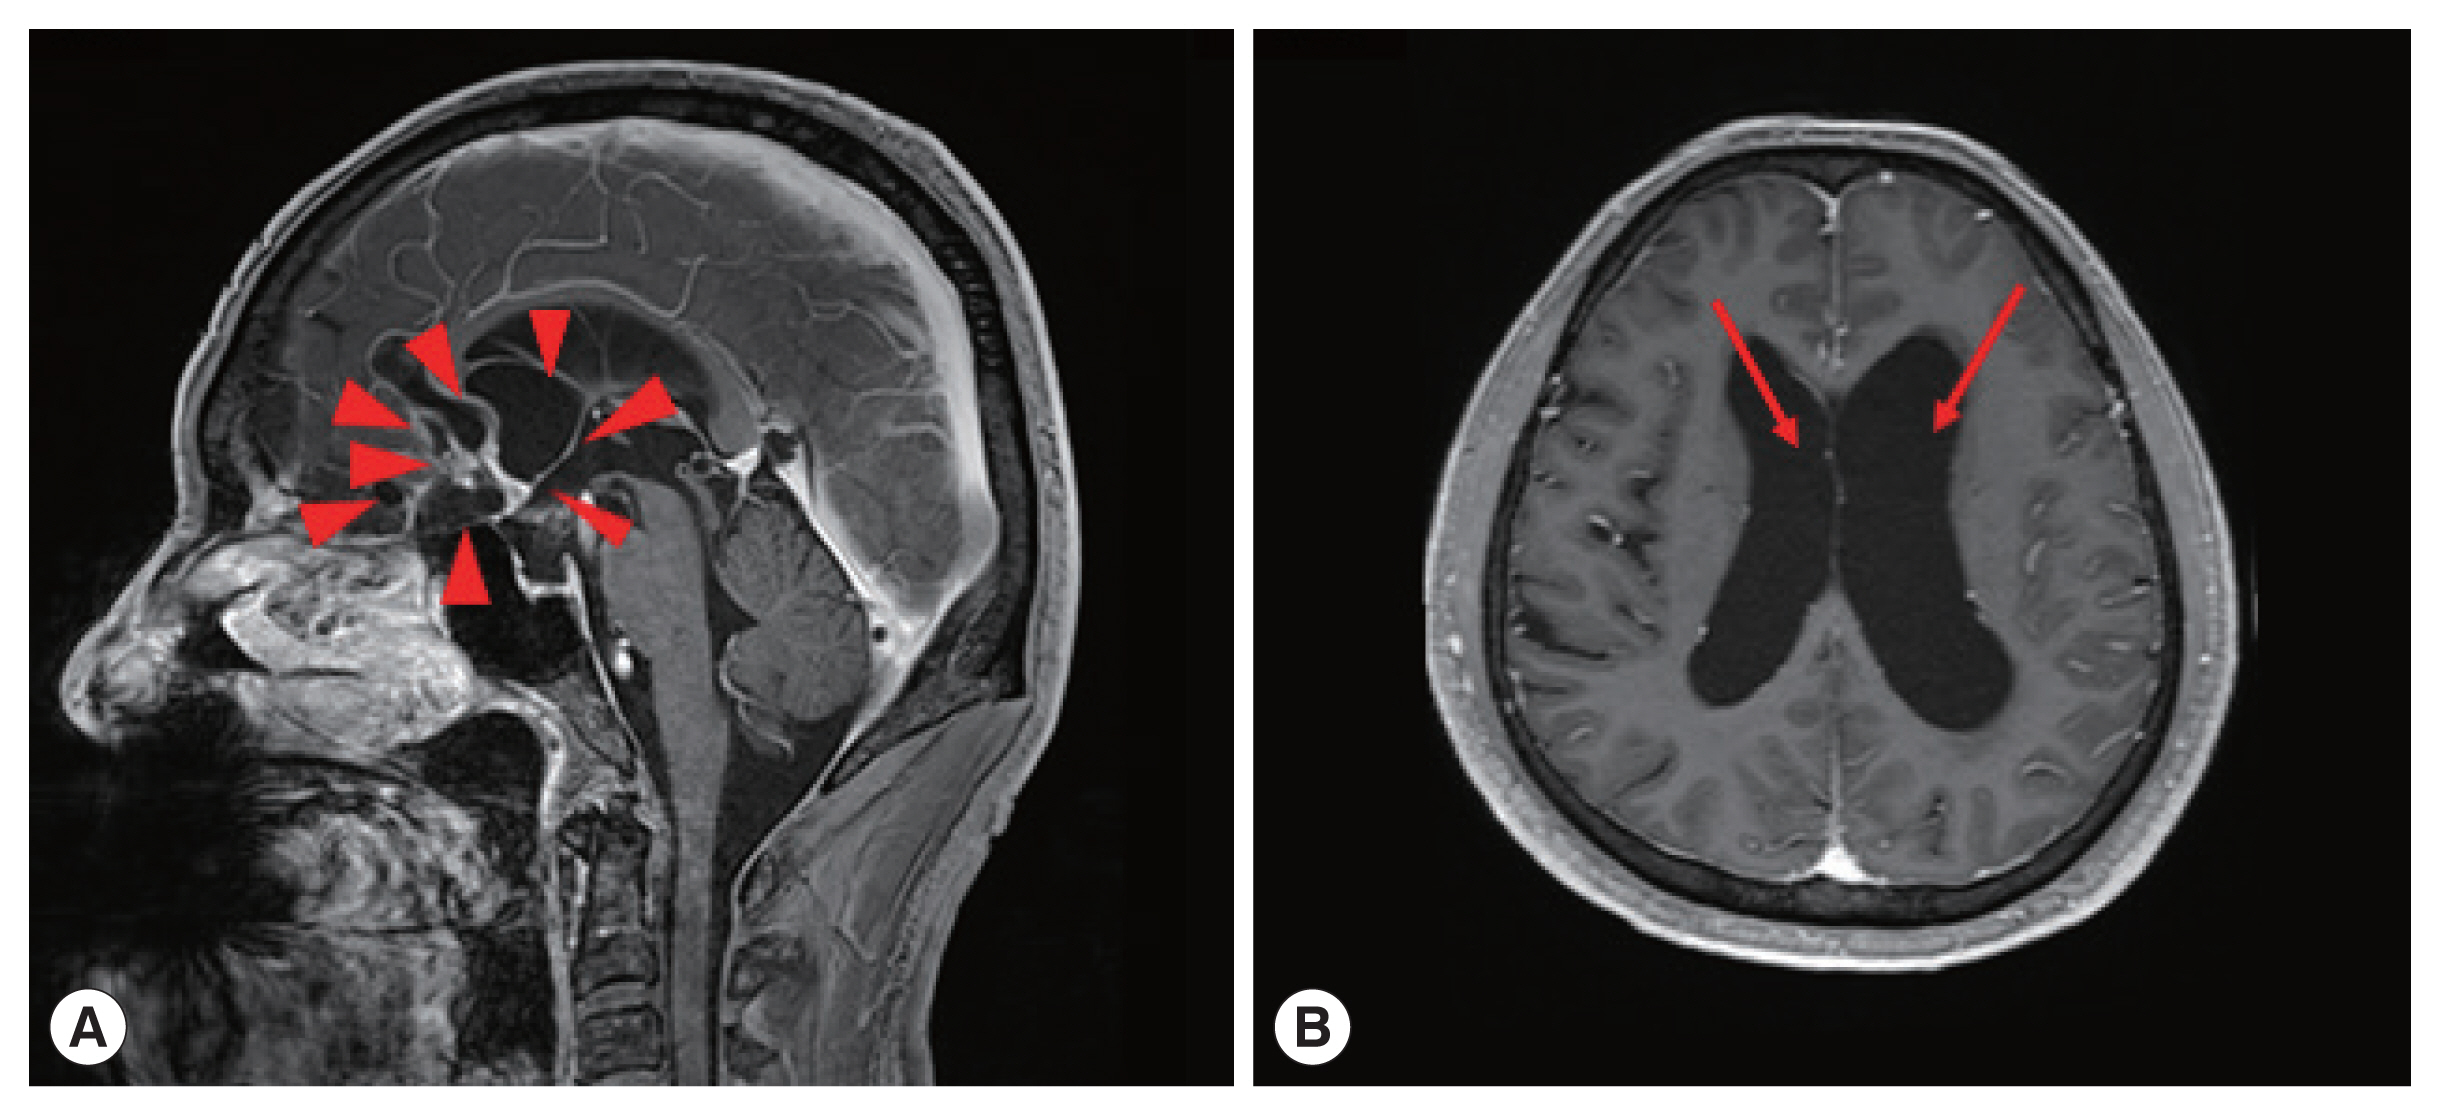

One of the patients was a 66 year old male with no previous medical history, who was admitted with symptoms of headache, vertigo, and gait disturbance. He had a history of working in Libya 35 years ago, and a history of travel to Vietnam (4 years ago) and China (1 year ago). CSF findings showed eosinophilic pleocytosis (CSF white blood cell count 29/μl, eosinophil percentage 18%), with elevated protein levels (89.3 mg/dl) and normal glucose levels (56 mg/dl). Brain MRI showed multiple cystic lesions with focal wall enhancement at both frontal base and subcallosal areas, with ventriculomegaly of both lateral ventricles and the 3rd ventricle (Fig. 1). Multiple calcific nodules in soft tissue were seen on chest imaging (Fig. 2). Based on these findings, immunodiagnostic testing for parasite infections were performed on the patient’s blood and CSF. Both serum and CSF cysticercus antibodies were positive, and the patient was diagnosed with neurocysticercosis. Albendazole was administered for 4 weeks, in combination with dexamethasone. Afterwards, his symptoms of headache improved, but his limping gait worsened, leading to a second course of therapy with albendazole, praziquantel, and steroids 3 months after the initial treatment. The patient showed slight improvement in symptoms before he was transferred to another hospital, and follow-up was lost.